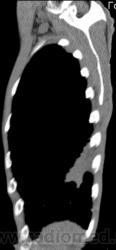

КТ - ОГК.  Ваше мнение коллеги?

На фоне консолидации полость без содержимого. Может быть всё что угодно, что сопровождается деструкцией. Нужны ещё томограммы в лёгочном окне.

Изображения выставлены все. Ваше мнение уважаемые коллеги?

6 и 9 срезы.